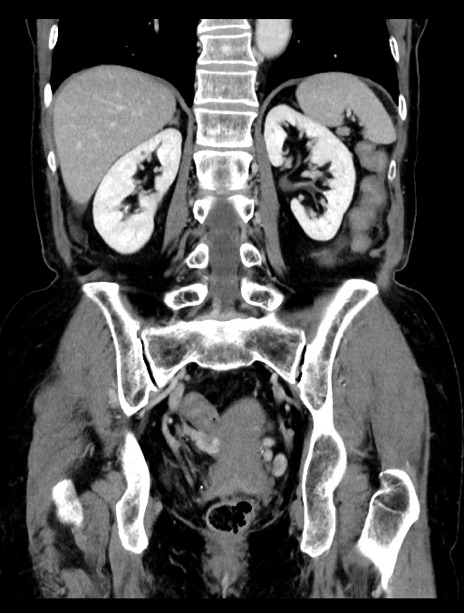

症例23(冠状断像)

【症例】70歳代女性

【主訴】下腹部痛・嘔吐

【現病歴】2日前より腹痛あり。昨日嘔吐あり。症状改善しないため来院。

【既往歴】胃GISTに対して胃部分切除後。

【身体所見】BT 37.1℃、BP 128/77mmHg、腹部:平坦・軟、下腹部に圧痛あり。

【データ】WBC 10200、CRP 0.31